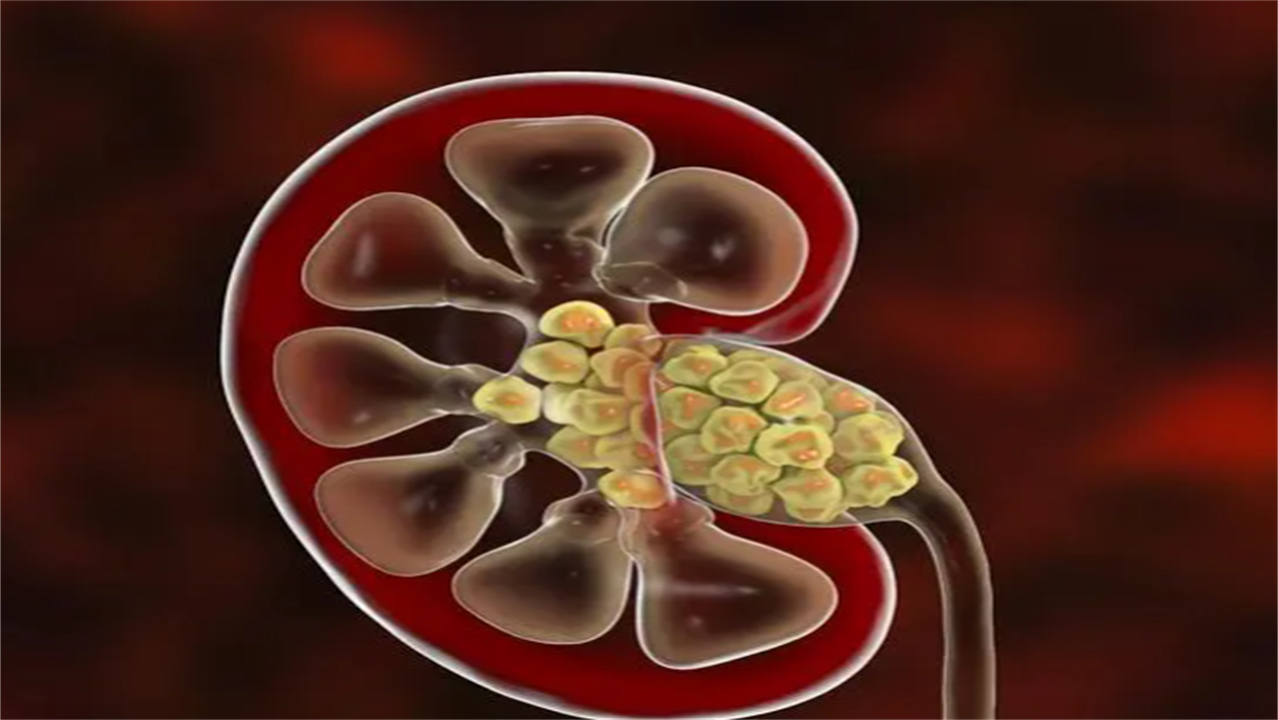

医生询问了小李症状持续的时间,初步判断小李的泌尿系统中可能长有结石。但是具体诊断结果,还需要结合泌尿系统彩超的结果进行判断,于是医生让小李去做了该检查。最终的检查结果显示,小李的左肾上出现了结石了。

不过好在结石的体积并不是很大,数量也不是很多,于是医生给小李开了一些具有溶石作用的药物治疗。

在拿到检查报告时,看到强回声光团,且后方伴有声影等文字时,说明大家体内存在结石病变。

若是存在肾脏上就是肾结石,如果出现在输尿管上就是输尿管结石。

肾脏和膀胱一般通过输尿管进行连接。若是输尿管上存在结石,可能就会导致肾脏产生的尿液无法顺利地进入到肾脏中储存起来,就容易导致肾脏积水,使肾脏的体积变大。